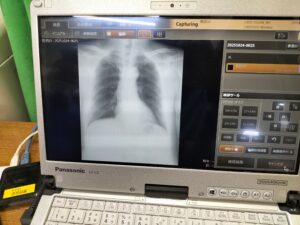

レントゲン撮影はポータブルのレントゲンの撮影のため入室から撮影含め、一人10秒程度で対応でき、椅子へ座っての撮影のため利用者全員レントゲン撮影ができました。